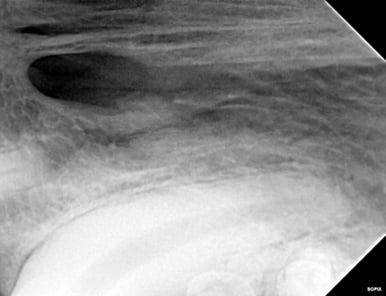

Below: During RCT - Radiograph finding working length to clean and measure canal

%20-%20March%202024/during%20RCT%20-%20finding%20working%20length.jpg?width=379&height=291&name=during%20RCT%20-%20finding%20working%20length.jpg)

Below: During RCT - finding master file size to clean canal walls appropriately and find master cone size of gutta percha

%20-%20March%202024/Radiograph%20of%20master%20file%20during%20RCT.jpg?width=386&height=296&name=Radiograph%20of%20master%20file%20during%20RCT.jpg)

A root canal procedure was performed on tooth 204, which was non-vital. To access the pulp chamber, a round surgical length bur was utilized. Upon reaching the pulp chamber, a radiograph was taken to ensure cleaning at the working length, which in this case was 38mm. Cleaning and shaping of the canal were carried out using Dentsply NiTi and LightSpeed files in alternation with suction aided sterile saline and sodium hypochlorite solutions.